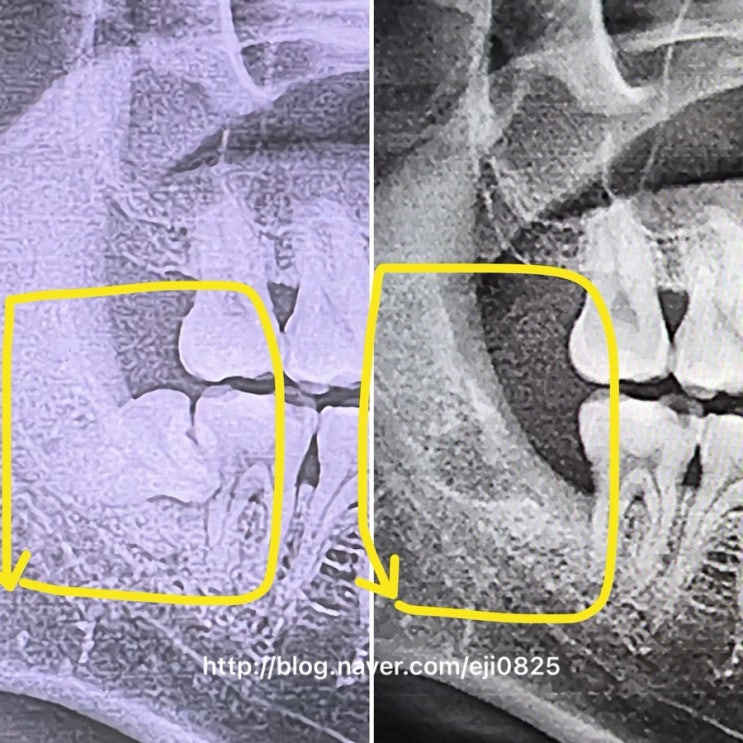

사랑니발치통증,발치비용|남편델꼬가서 둘다 사랑니뽑고온 찐후기|매복사랑니발치후기|사랑니잘뽑는곳

본격 사랑니발치 찐후기글쓰기에 앞서서 2년전 사랑니발치 찐후기를 썼던 내 소중한 글이 강제삭제된썰을 ...